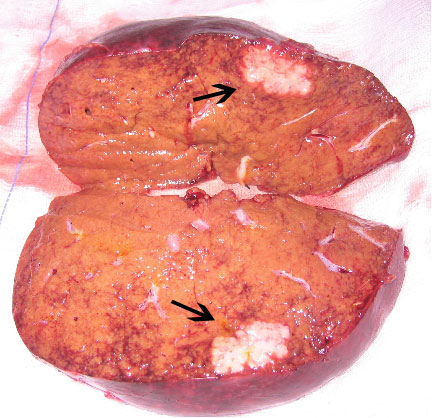

Οι μεταστάσεις ανιχνεύονται συχνότερα στο δεξιό λοβό, ίσως λόγω του γεγονότος ότι είναι μεγαλύτερος από τον αριστερό. Ωστόσο, το 60% των ασθενών που έχουν διαγνωσθεί με μεταστατική νόσο έχουν εντοπίσεις και στους δύο λοβούς. Όταν διαπιστώνονται, οι ηπατικές μεταστάσεις έχουν μέγεθος 3 με 5 εκατοστά (εικόνα 1). Σε ορισμένες περιπτώσεις όμως μπορούν να ξεπεράσουν και τα 10 εκατοστά.

Εικόνα 1. Τυπική ηπατική μετάσταση μεγέθους 3,5 εκατοστών (σημειώνεται με μαύρα βέλη) σε οβελιαία τομή παρασκευάσματος δεξιού ηπατικού λοβού.